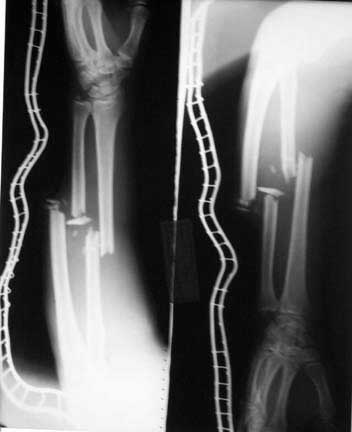

I did a debridement and could get a satisfactory field for internal stabilisation. The options I had kept were Ex fix, antegrade nailing and retrograde nailing. Had to be prepared for an arterial exploration if required. The vascular bundle was lying exposed through the compounding wound and could get the pulse beyond the fracture site. For this purpose I used a radioluscent flat table and did not use traction table intra-op.

After debridement I did a retrograde nailing using a solid SIGN nail. I thought this gave me the best chance to do with minimal disturbance to the head end on a flat table where the patient was supine. Sepsis to the knee was a worry but since I was using a solid nail I was fairly confident that the two area of concern( the fracture site and knee joint) will be sparated and will not spread infection from one place to other.

Post op patient is doing well but for mildly raised cpk secondary to muscle damage. This is settling.